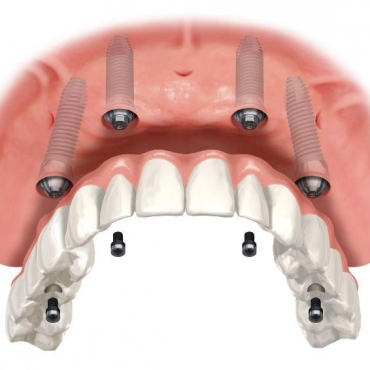

Τα οδοντικά εμφυτεύματα αντικαθιστούν τις ρίζες των δοντιών παρέχοντας ένα ισχυρό θεμέλιο για τη σταθερή ή κινητή αποκατάσταση των απολεσθέντων δοντιών, εφάμιλλων των φυσικών.

Επειδή γίνονται κομμάτι του εαυτού σας τα εμφυτεύματα εξαλείφουν την ταλαιπωρία των κινητών οδοντοστοιχιών.

Οι κινητές οδοντοστοιχίες δυσκολεύουν τη μάσηση. Τα οδοντικά εμφυτεύματα λειτουργούν σαν τα δικά σας δόντια, επιτρέποντάς σας να τρώτε τα αγαπημένα σας φαγητά χωρίς πόνους και ενοχλήσεις. Για ακόμα μια φορά ο κίνδυνος εκτροπής της ολικής οδοντοστοιχίας καθώς εσείς τρώτε παύει να υπάρχει.